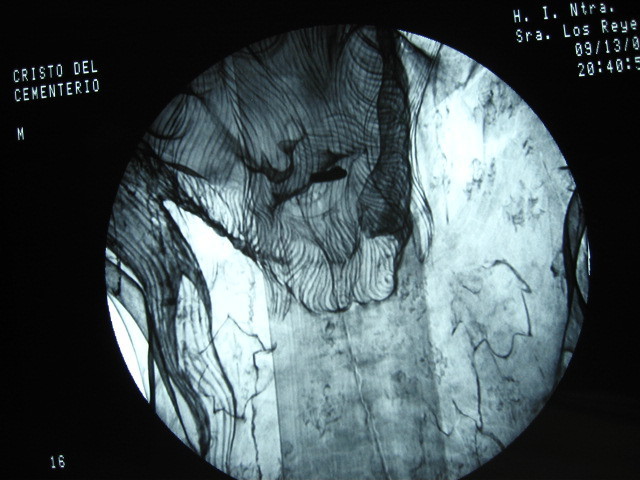

Restauraciones recientes

Echa un vistazo a esta galería de arte virtual en la que se pueden ver algunas de las restauraciones que he hecho. Quizá descubras algo que te interese durante la visita... o pienses en alguna obra de arte que sepas que está algo deteriorada, para que te hagas una idea de cómo podría quedar si se pone en buenas manos.